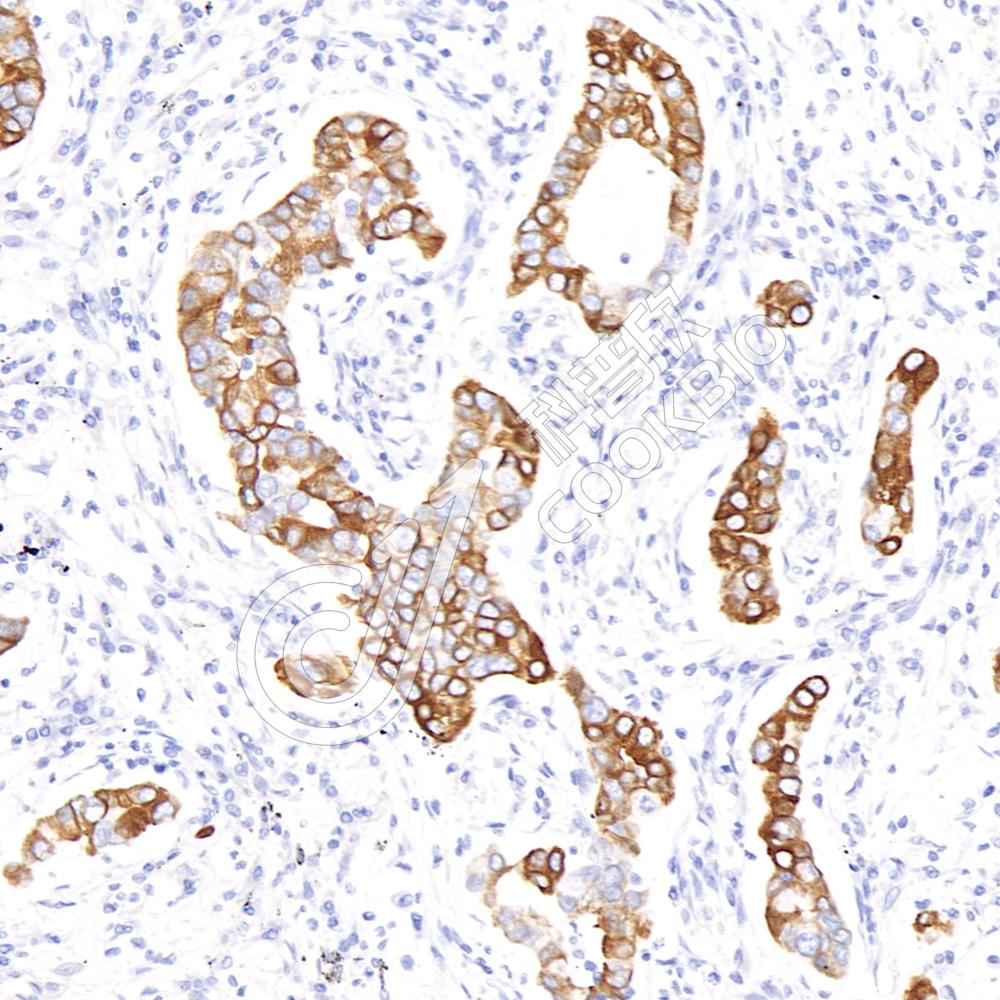

IF检测Cytokeratin 5蛋白(货号 K1333738)(红色).

样品: 人乳腺癌, 4%多聚甲醛 (货号KSG1101) 固定12-24小时.

抗原修复: Tris-EDTA抗原修复液(pH 9.0) (KSG1203), 98℃, 20分钟.

封闭: 3% BSA(货号KSGC305010)的PBS溶液, 室温孵育30分钟.

—抗: 1: 2000稀释, 4℃ 孵育过夜.

二抗: Cy3标记山羊抗兔IgG (H+L) (货号KB63909), 1: 300稀释, 室温孵育1小时.